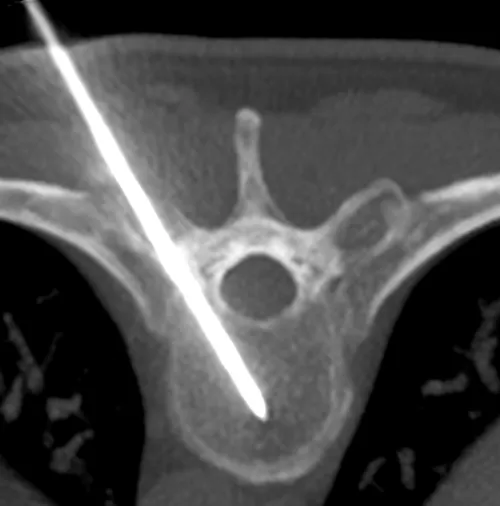

1. Trocard de cimentoplastie en place dans la vertèbre